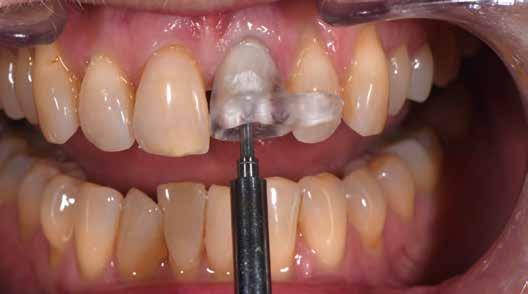

1. kép: Preoperatív szituáció.

Pácienseset

33 éves páciens konzultált a rendelőben 3 évig tartó fogszabályozása elemeinek eltávolításáról szájából. A kárieszek eltüntetésén kívül optimalizálni szerette volna esztétikai kinézetét. Az első esztétikai elemzés a frontfogak kedvezőtlen hossz-szélesség arányát mutatta (1. kép). A bal felső szemfogat a pulpa elhalása következtében endodonciai kezelésnek is alá kellett vetni.

Klinikai kezelés

A gyökérkezelést és a kárieszek megszűntetését követően kompozittömések készültek, majd preparálták a restaurálandó frontfogakat (3. kép). Ideiglenes koronák is szájba kerültek (4. kép), a jobb kismetszőt meghosszabbították. A fogínylefutás szimmetriáját az ideiglenes koronák megtámasztása segítette. A fogak és íny kívánt szimmetriáját elérve véglegesítették a preparációt (5. kép) és elkészültek a lenyomatok.